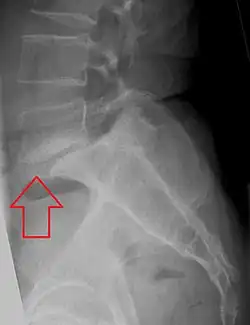

Retrolisthesis

A retrolisthesis is a posterior displacement of one vertebral body with respect to the subjacent vertebra to a degree less than a luxation (dislocation). Retrolistheses are most easily diagnosed on lateral x-ray views of the spine. Views, where care has been taken to expose for a true lateral view without any rotation, offer the best diagnostic quality.

Retrolistheses are found most prominently in the cervical and lumbar region, but can also be seen in the thoracic area.